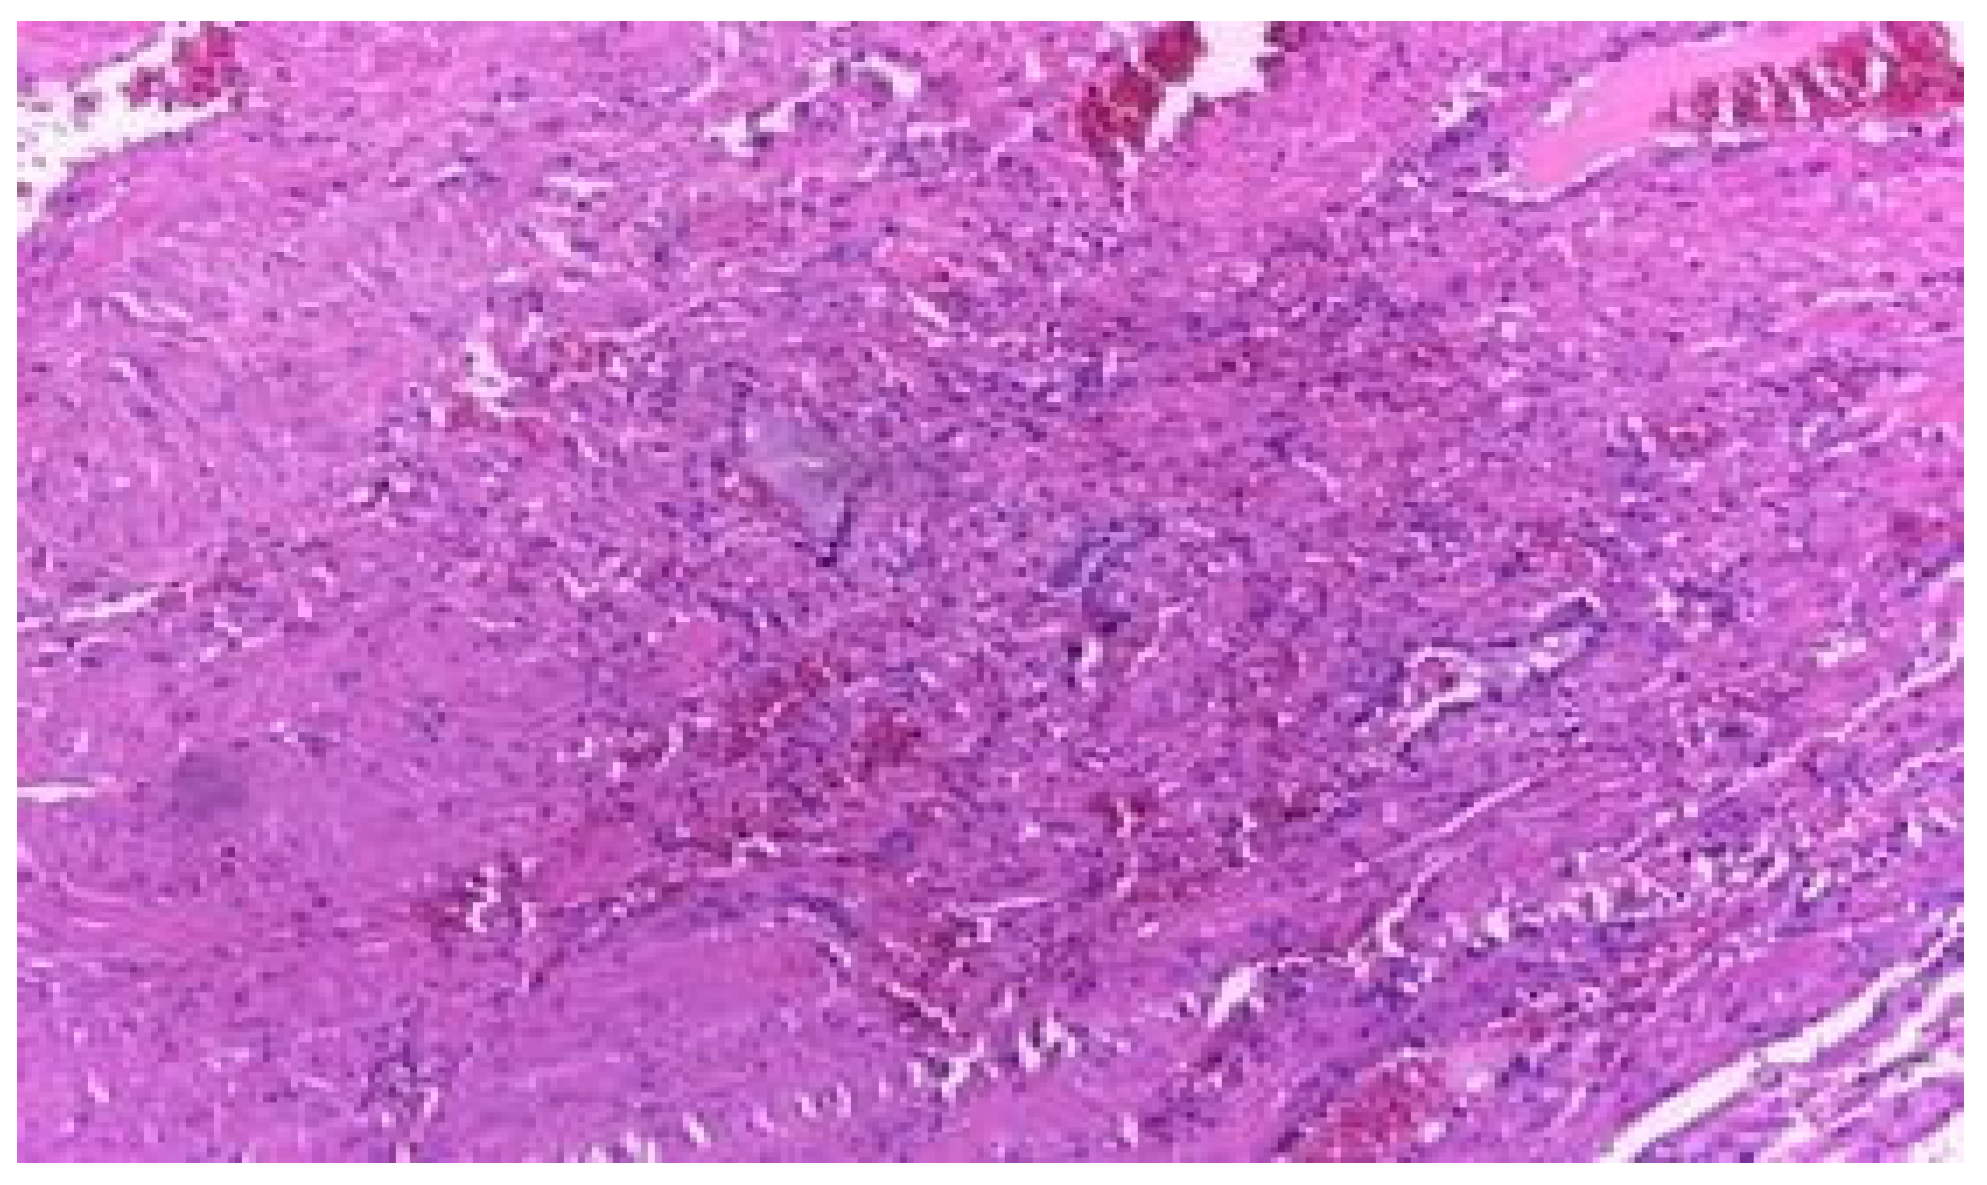

- This observation of inverse proportionality between the uterine thickness and the risk of rupture/dehiscence of the scar seems to be correlated with the histopathological features of the cesarean section scar.